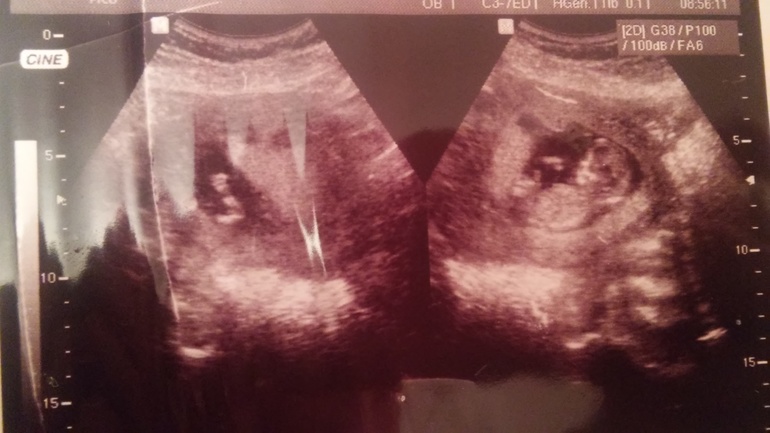

3. На учет стала в 12 недель, сразу и анализы и узи прошла, все ттт хорошо, намерили дитя аж на 18 см!!! Это нормально?)) думаю, в любом случае лучше богатырь, чем хилик))

На снимке машет ручкой "привет"